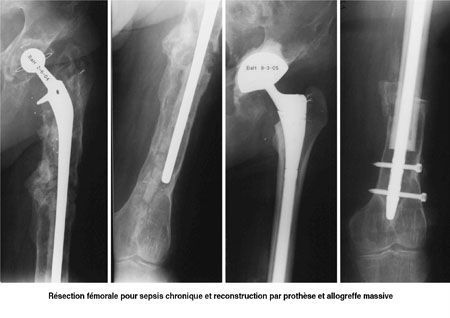

Mise au point Intérêt d'une banque de tissus en chirurgie orthopédique , Olivier Cornu Cliniques Universitaires St-Luc, Université Catholique de Louvain, Bruxelles, Belgique , Vincent Druez Clinique Saint-Jean, Bruxelles, Belgique , Christian Delloye Cliniques Universitaires St-Luc, Université Catholique de Louvain, Bruxelles, Belgique N°154 - Mai 2006 ● 16 min de lecture